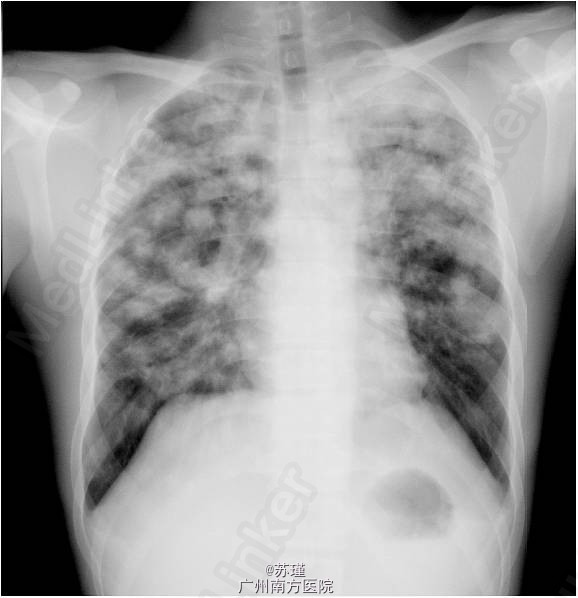

男,33岁,因反复咳嗽半年余,发热2个月入院, 患者半年前感冒后开始出现咳嗽,以干咳为主,清晨咳嗽较多,同时伴有乏力、盗汗。无痰,无发热,无咯血、无胸闷、气促等不适。 2个月前患者开始出现发热,,以午后发热多见,体温最高达38.5℃,未予特殊处理体温可自行降至正常,同时伴有乏力、盗汗及气促,可平卧,无胸痛、咯血、无胸闷,无腹痛、腹泻,无恶心、呕吐,遂再次到当地医院就诊,查胸片见双肺散在结节影,予收入院治疗 气管镜抗酸杆菌(+)